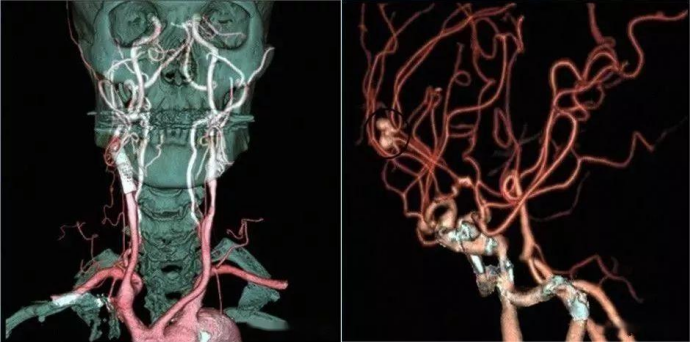

頭、頸血管CTA成像